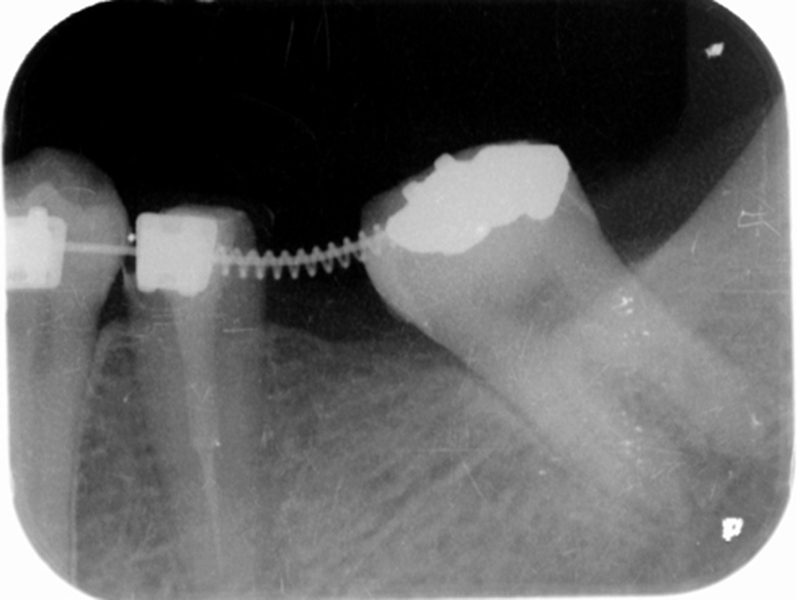

▼ ケース3.Upright症例

治療前

矯正開始~矯正終了

矯正開始~矯正終了ビフォー

矯正開始~矯正終了アフター